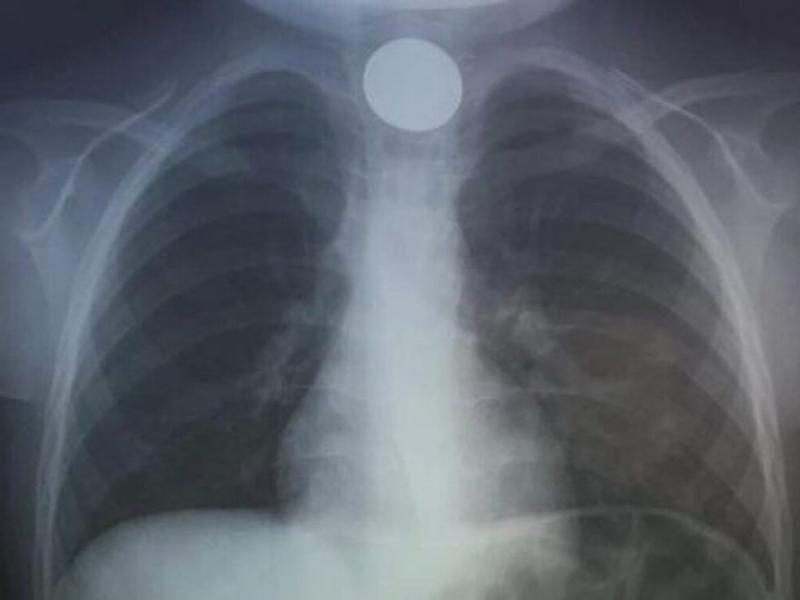

κερμα

Πρωτοχρονιάτικη περιπέτεια είχε ένα 4χρονο αγόρι, καθώς κατάπιε ένα ξένο σώμα και μεταφέρθηκε στο νοσοκομείο παραμονή Πρωτοχρονιάς.

Σύμφωνα με πληροφορίες από το cretapost, το 4χρονο παιδί είχε καταπιεί ένα κέρμα και δεν μπορούσε να αναπνεύσει.

Άμεσα οδηγήθηκε στο ΠΑΓΝΗ με τους γιατρούς να προχωρούν σε επείγουσα αφαίρεση η οποία στέφθηκε με επιτυχία.